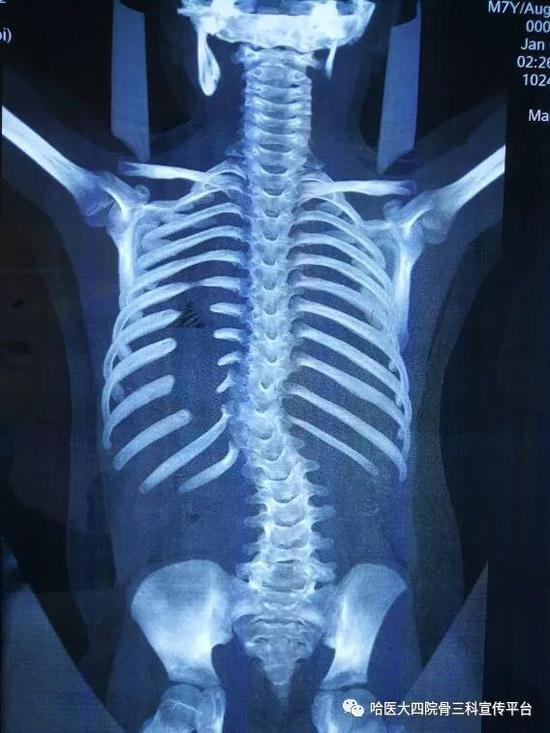

先天性脊柱畸形之:半椎体(一)

先天性脊柱侧弯2半椎体畸形

半椎体畸形是一种由于胎儿期中胚层发育不良的先天性疾病,常好发于

半椎体畸形,第13胸椎